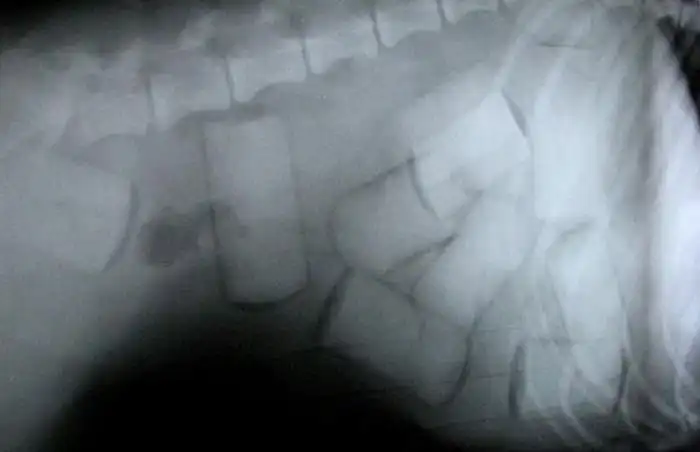

Контрабандисты, перевозящие наркотики, постоянно придумывают новые способы доставки смертоносного груза в различные страны, но, к счастью, не всегда их находчивость ведет к успеху.